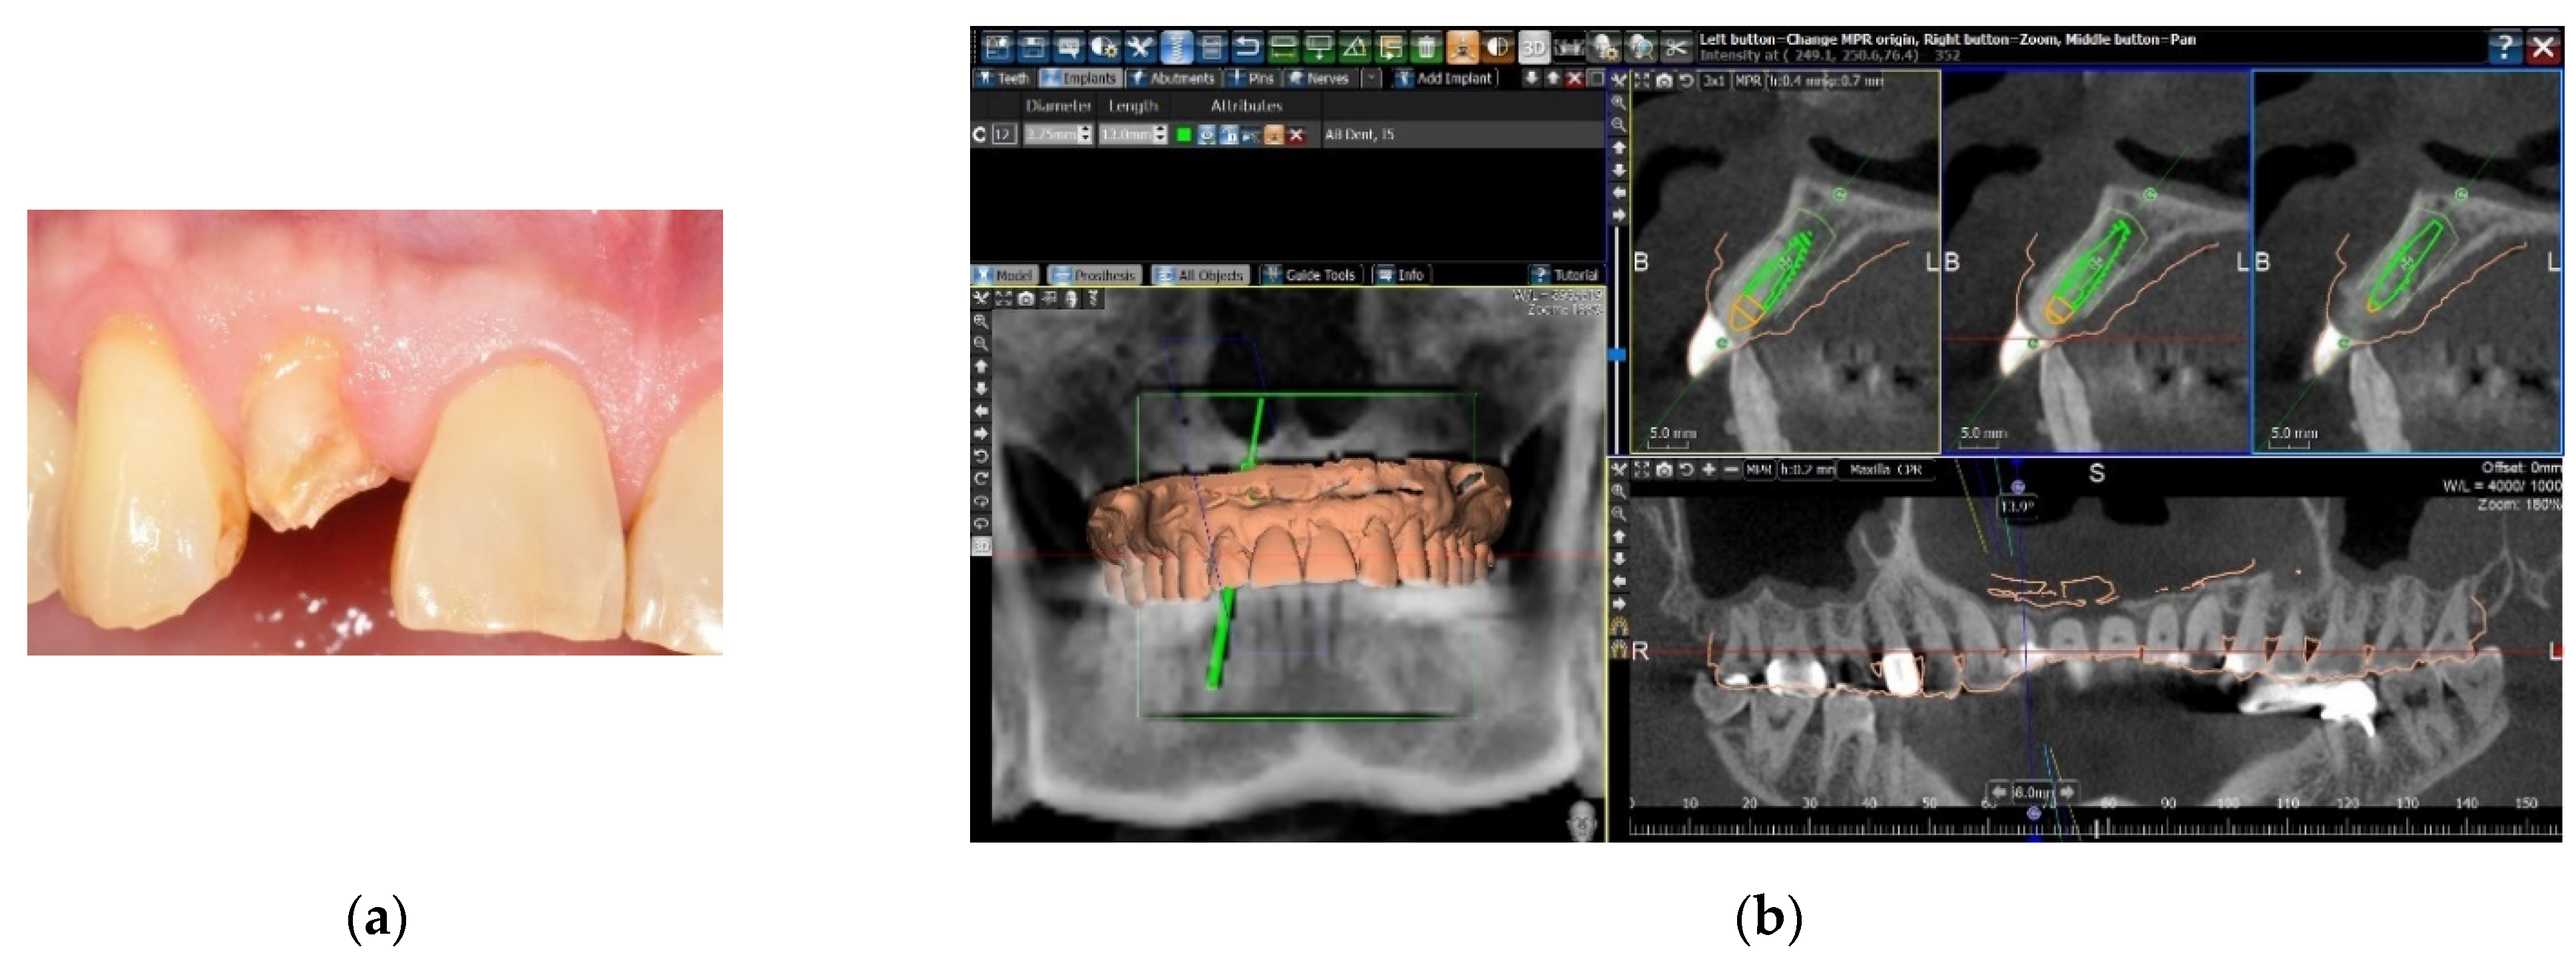

Two methods were used for the image registration of the digital dental cast and the dataset of the CBCT scan. The first was to take an impression of the patient’s dental arch with polyether impression material (Impregum Penta Soft, 3M Deutschland GmbH, Neuss, Germany), and a stone cast was poured. The stone cast was optically scanned with a desktop model scanner (inEos X5, Sirona Dental Systems GmbH, Bensheim, Germany) to obtain a digital dental cast in the form of Standard Tessellation Language (STL) files. A CBCT scan of the patient was taken with a large field-of-view CBCT scanner (3D eXam, KaVo Dental, Biberach, Germany), and the Digital Imaging and Communication in Medicine (DICOM) files were attained. The two data sets were uploaded into implant planning software (BenQ AB Guided Service, AB Dental, Ashdod, Israel). The two digital images were then superimposed with the registration tool of the software by setting five registration points on the corresponding dental surfaces of the two digital images (Figure 1).

Figure 1. Matching the digital dental cast and the CBCT scan by registration of dental surface images. (a) A patient with a fractured right maxillary lateral incisor. (b) The digital dental cast and the CBCT scan were superimposed by setting registration points on the corresponding dental surfaces of the two digital images.